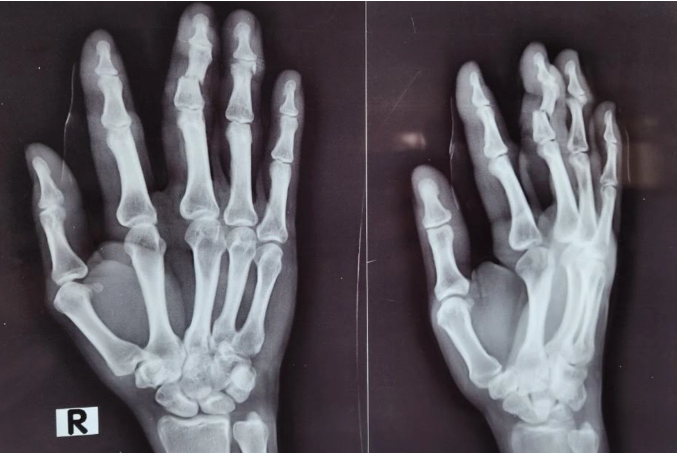

| Ảnh chụp X-quang đánh giá các vết thương ở bàn tay của người phụ nữ (Ảnh: BV). |